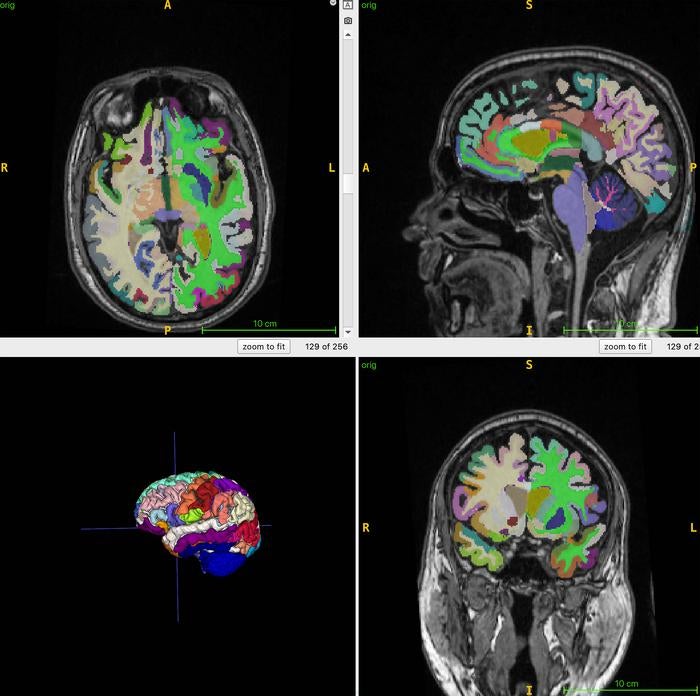

Looking at the health of 1,164 healthy men and women using whole-body MRI scans, the researchers were able to determine the fattiest parts of the body. Next, they used an AI algorithm to determine the participants’ ratio of muscle to fat, as well as their subsequent brain age.

open image in galleryThe doctors took MRI scans, feeding it into an AI algorithm to help determine patients’ brain ages (Cyrus Raji, M.D., Ph.D., and RSNA)More reps, fewer years